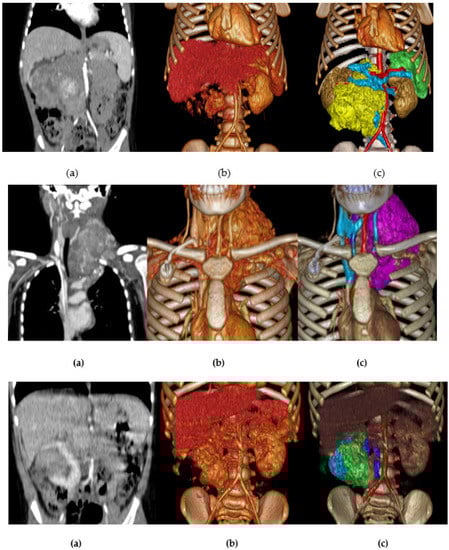

3.1.2. Volume Rendering and Cinematic Rendering

3.1.3. Three-Dimensional Virtual Simulations (CAD Models)

| Case #1 | 3 | F | Abdominal neuroblastoma | Laparotomy |

| Case #2 | 11 | F | Thoracic Inlet neuroblastoma | Trap Door |

| Case #3 | 2 | F | Bilateral Wilms tumor (nephron-sparing surgery) | Bilateral Transverse Laparotomy |